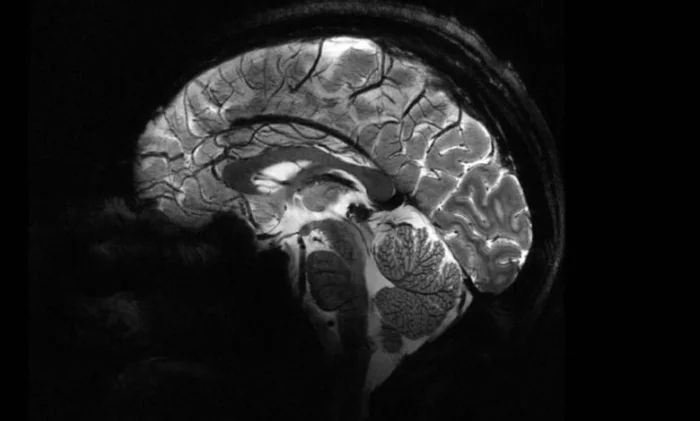

Такая высокая магнитная мощность обеспечивает лучшее качество изображения. Пространственное разрешение сканирования составляет 200 микрометров (мкм), то есть прибор может определить две точки, находящиеся на расстоянии всего 200 мкм друг от друга. Такое высокое разрешение обеспечивает более структурированные и точные изображения, что позволяет врачам более эффективно проводить исследования.

Высокая магнитная сила Iseult также означает, что изображения можно получить за рекордно короткое время (четыре минуты). При использовании обычного оборудования этот процесс занимает в среднем от 30 до 45 минут для мозга. «Мы можем получать изображения в масштабе нескольких тысяч нейронов, что означает, что всего за несколько минут мы можем получить очень точные детали анатомии мозга, его связей и активности«, — объясняет Александр Виньо, директор по исследованиям CEA.